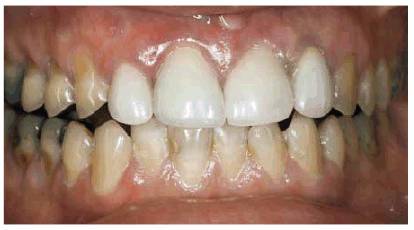

patient (Figures 17-1A to

C

Figure 17-1A to C: These photographs illustrate the complex dental condition of a 71-year-old male: (A) The palatal cervical regions of the maxillary anterior teeth exhibit sharp, wedge-like lesions that are characteristic of abfraction. These areas would be difficult, if not impossible, to have resulted from toothbrush abrasion. (B) The buccal aspects of the maxillary posterior teeth show smooth, concave configurations that are consistent with toothbrush abrasion and/or erosion. (C) The buccal surfaces of the mandibular teeth have lesions that possess components of both abfraction (sharp margins in the occlusal regions) and abrasion (concave geometry and gingival recession in the cervical regions).